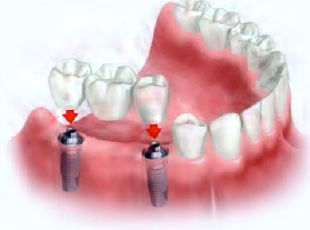

Para os pacientes que possuem boa quantidade óssea, atualmente já é possível a realização de Implante Imediato. Nestes casos o implante é colocado, e a prótese provisória pode ser instalada imediatamente ou em até 3 dias.